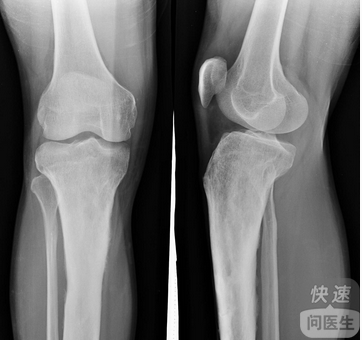

核心提示:长假之后各种疾病接踵而来,其中滑膜炎等关节疾病最为常见。那么你知道治疗滑膜炎的方法吗?在刚刚过去的十一长假,下沙的余先生在香港暴走4天,每天都是25000到26000步左右。几乎天天都是冠军,但是这个冠军给他带来...